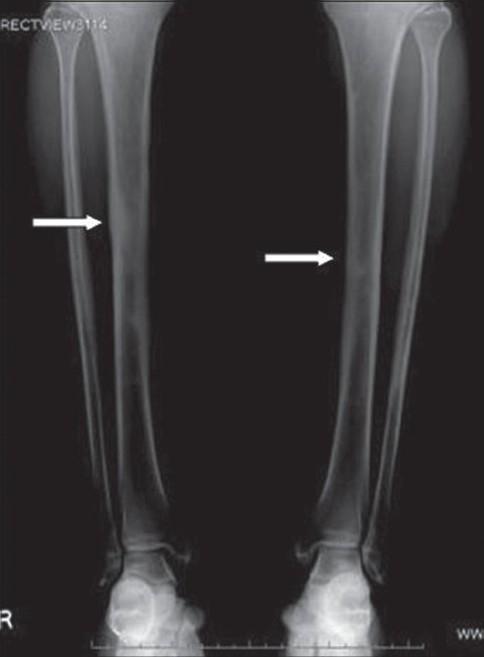

Ribbing disease is a rare sclerosing dysplasia that involves long tubular bones, especially the tibia and femur. It occurs after puberty and is reported to be more common in women. In this article we describe how Ribbing disease can be differentiated from diseases like Engelmann-Camurati disease, van Buchem disease, Erdheim-Chester disease, osteoid osteoma, chronic osteomyelitis, stress fracture, etc.

里宾病是一种罕见的骨硬化发育异常疾病,累及长管状骨,尤其是胫骨和股骨。它在青春期后发病,据报道在女性中更为常见。在本文中,我们描述了如何将里宾病与恩格尔曼-卡穆拉蒂病、范布赫姆病、厄尔德海姆-切斯特病、骨样骨瘤、慢性骨髓炎、应力性骨折等疾病相鉴别。